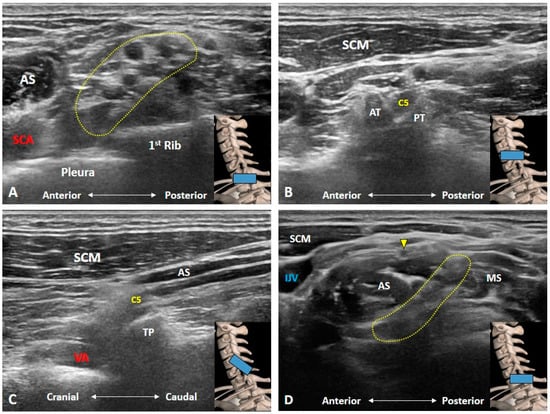

2. Anatomy

3. Imaging for Normal BP

3.1. Should We Start the Scanning Cranially?

3.2. Is the C7 Transverse Process Easily Recognized?

3.3. How Can We Locate the C8 and T1 Roots?

3.4. How Can We Better Visualize Cervical Anterior Rami during the Scanning Process?

3.5. Which Vascular Structure(s) Should We Be Aware Of?

3.6. Which Branches of the BP Can Be Seen in the Cervical Region?